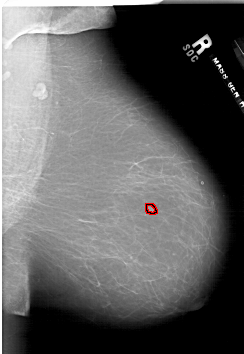

A_1911_1.RIGHT_MLO

RIGHT_MLO LINES 6361 PIXELS_PER_LINE 4381 BITS_PER_PIXEL 12 RESOLUTION 43.5 OVERLAY

FILE: A_1911_1.RIGHT_MLO.OVERLAY

TOTAL_ABNORMALITIES 1

ABNORMALITY 1

LESION_TYPE MASS SHAPE LOBULATED MARGINS CIRCUMSCRIBED

ASSESSMENT 3

SUBTLETY 2

PATHOLOGY BENIGN

TOTAL_OUTLINES 1

BOUNDARY